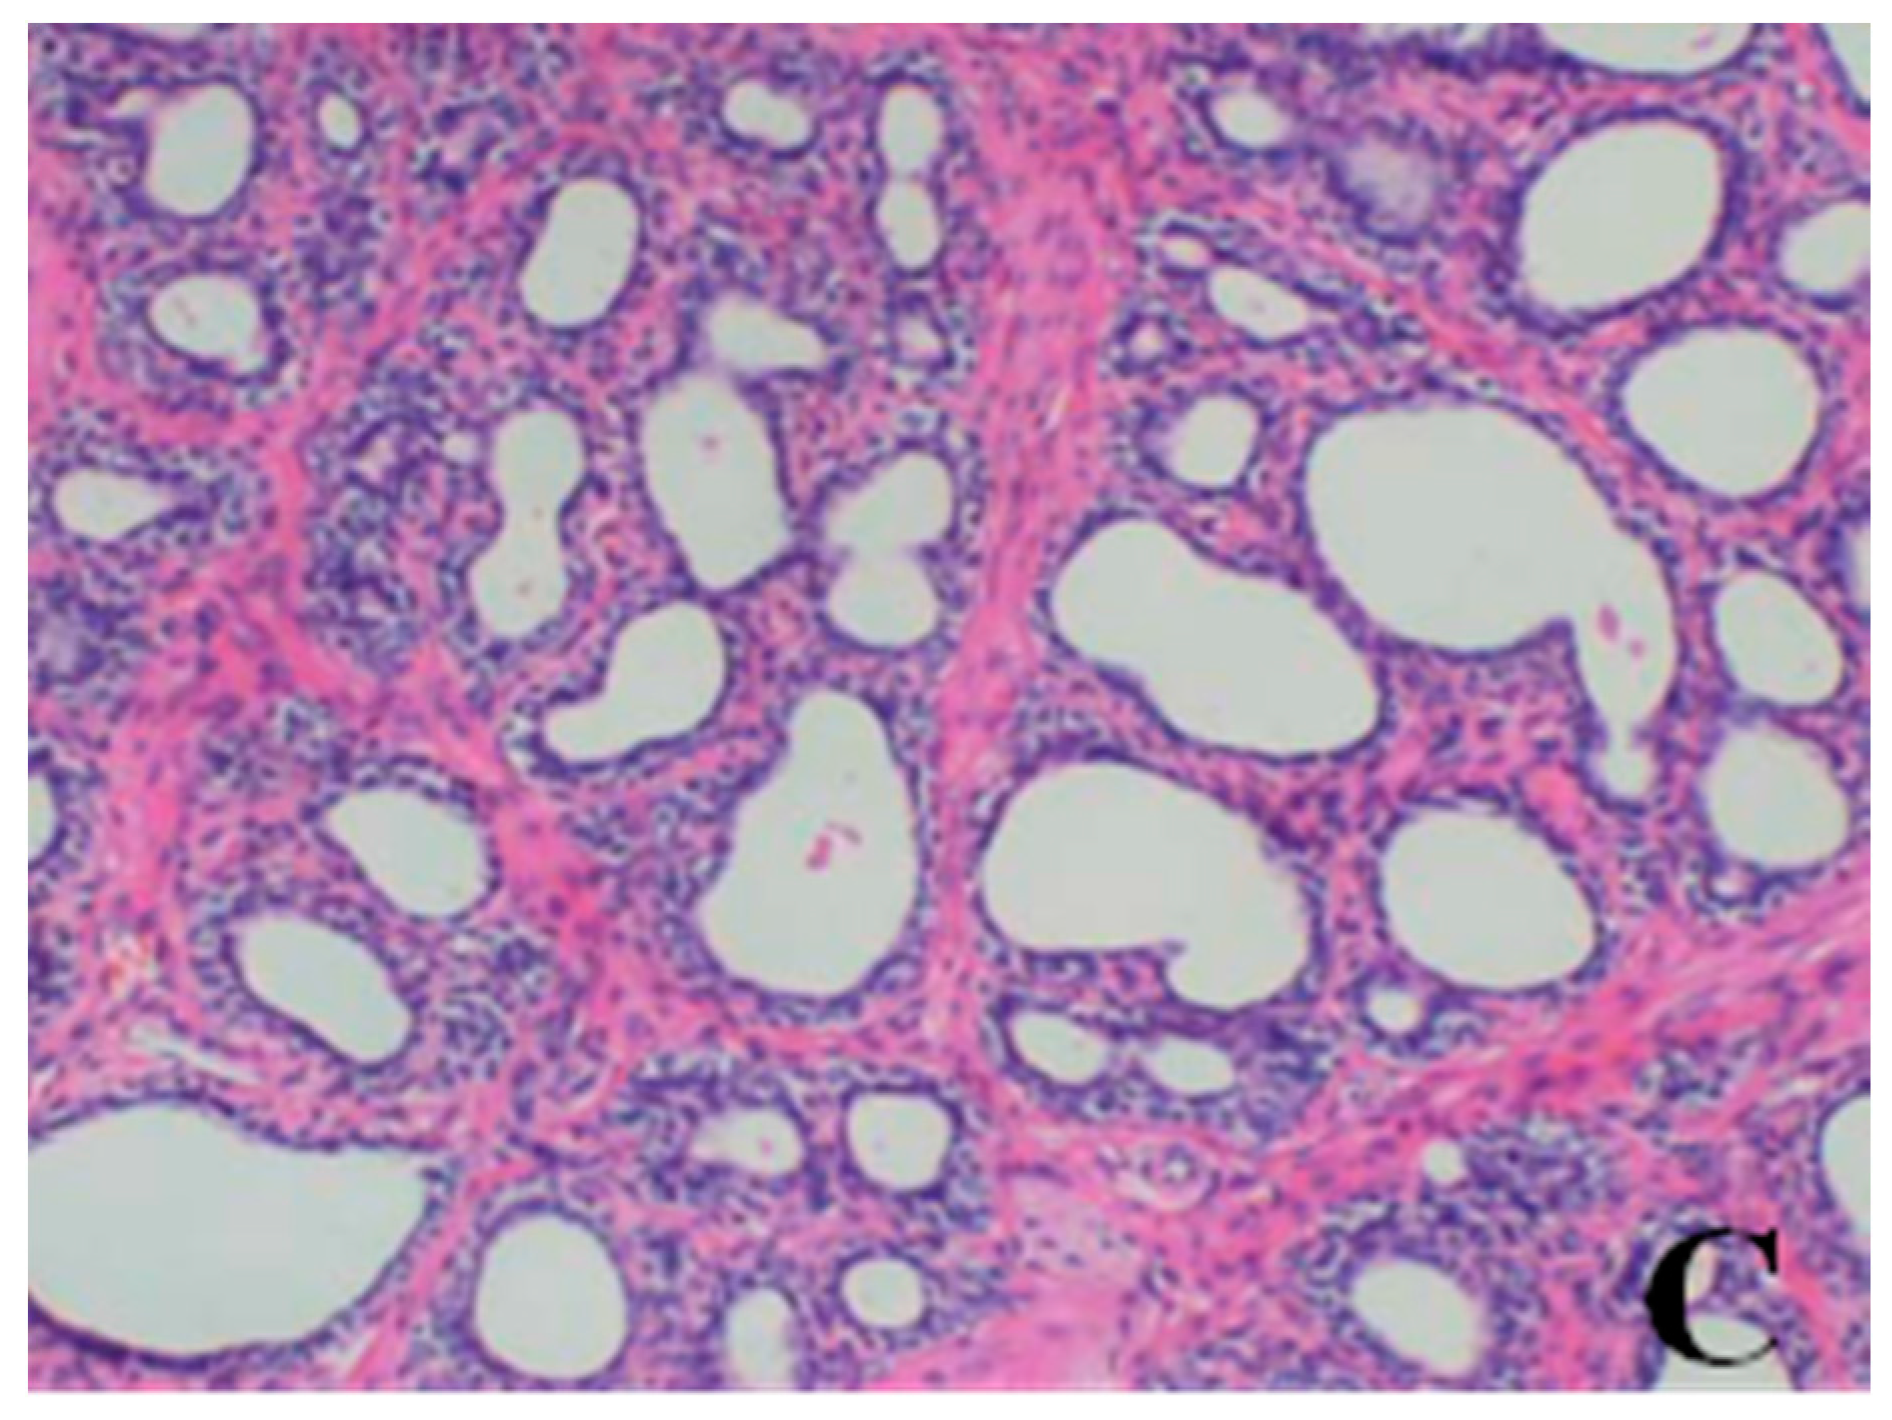

Histopathological Findings

Male reproductive organs (testis, epididymis and prostate)

- Testis: The numbers of seminiferous tubules decreased in dogs belonging to the 80- and 40-mg/kg dose groups, while the tubule lumen decreased and had reduced numbers and types of spermatogenic cells when compared with the control group. Only spermatogonia and some primary and secondary spermatocytes were observed, and there were no mature sperm compared with the control group.

- Epididymis: When compared with the control group, there was a notable lack of mature sperm cells and secretions in the epididymal lumen, as well as a decrease in epididymis lumen size, an irregular shape of the epididymal lumen and an increase in the connective tissue in the interstitium observed in dogs in the 80- and 40-mg/kg dose groups.

- Prostate: When compared with the control group, a reduction in the numbers and size, a thinner epithelium, narrower glandular cavity and increase in the connective tissue in the interstitium were observed in the prostatic acini of dogs in the 80- and 40-mg/kg dose groups.

| Organ | Findings | Dose (mg/kg/day) | ||||

|---|---|---|---|---|---|---|

| 0 | 5 | 20 | 40 | 80 | ||

| Lung | large confluent bronchopneumonia | 0/4 | 0/4 | 0/4 | 2/4 | 2/4 |

| Bone marrow of sternum | decrease in hematopoietic cell numbers | 0/4 | 0/4 | 0/4 | 2/4 | 3/4 |

| Testis | Reduction in numbers and types of spermatogenic cells | 0/2 | 0/2 | 0/2 | 2/2 | 2/2 |

| Epididymis | lack of mature sperm and secretions in the epididymal lumen as well as decrease of epididymal lumen size | 0/2 | 0/2 | 0/2 | 2/2 | 2/2 |

| Prostate | reduction in numbers and size, thinner epithelium, narrowing of the glandular cavity of prostatic acini | 0/2 | 0/2 | 0/2 | 2/2 | 2/2 |